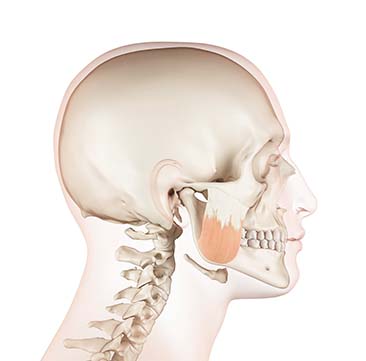

Definition

양악 재수술이란?

양악 재수술은 기존 양악수술 이후 기능적 문제나 얼굴 균형 불만족 등이 발생할 경우, 정밀 진단을 통해 문제 원인을 찾아 다시 교정하거나 턱뼈 위치를 조정하는 수술입니다.

초기 수술 후 발생할 수 있는 교합 이상, 안면 비대칭, 턱관절 문제 등이 주요 재수술 대상입니다.